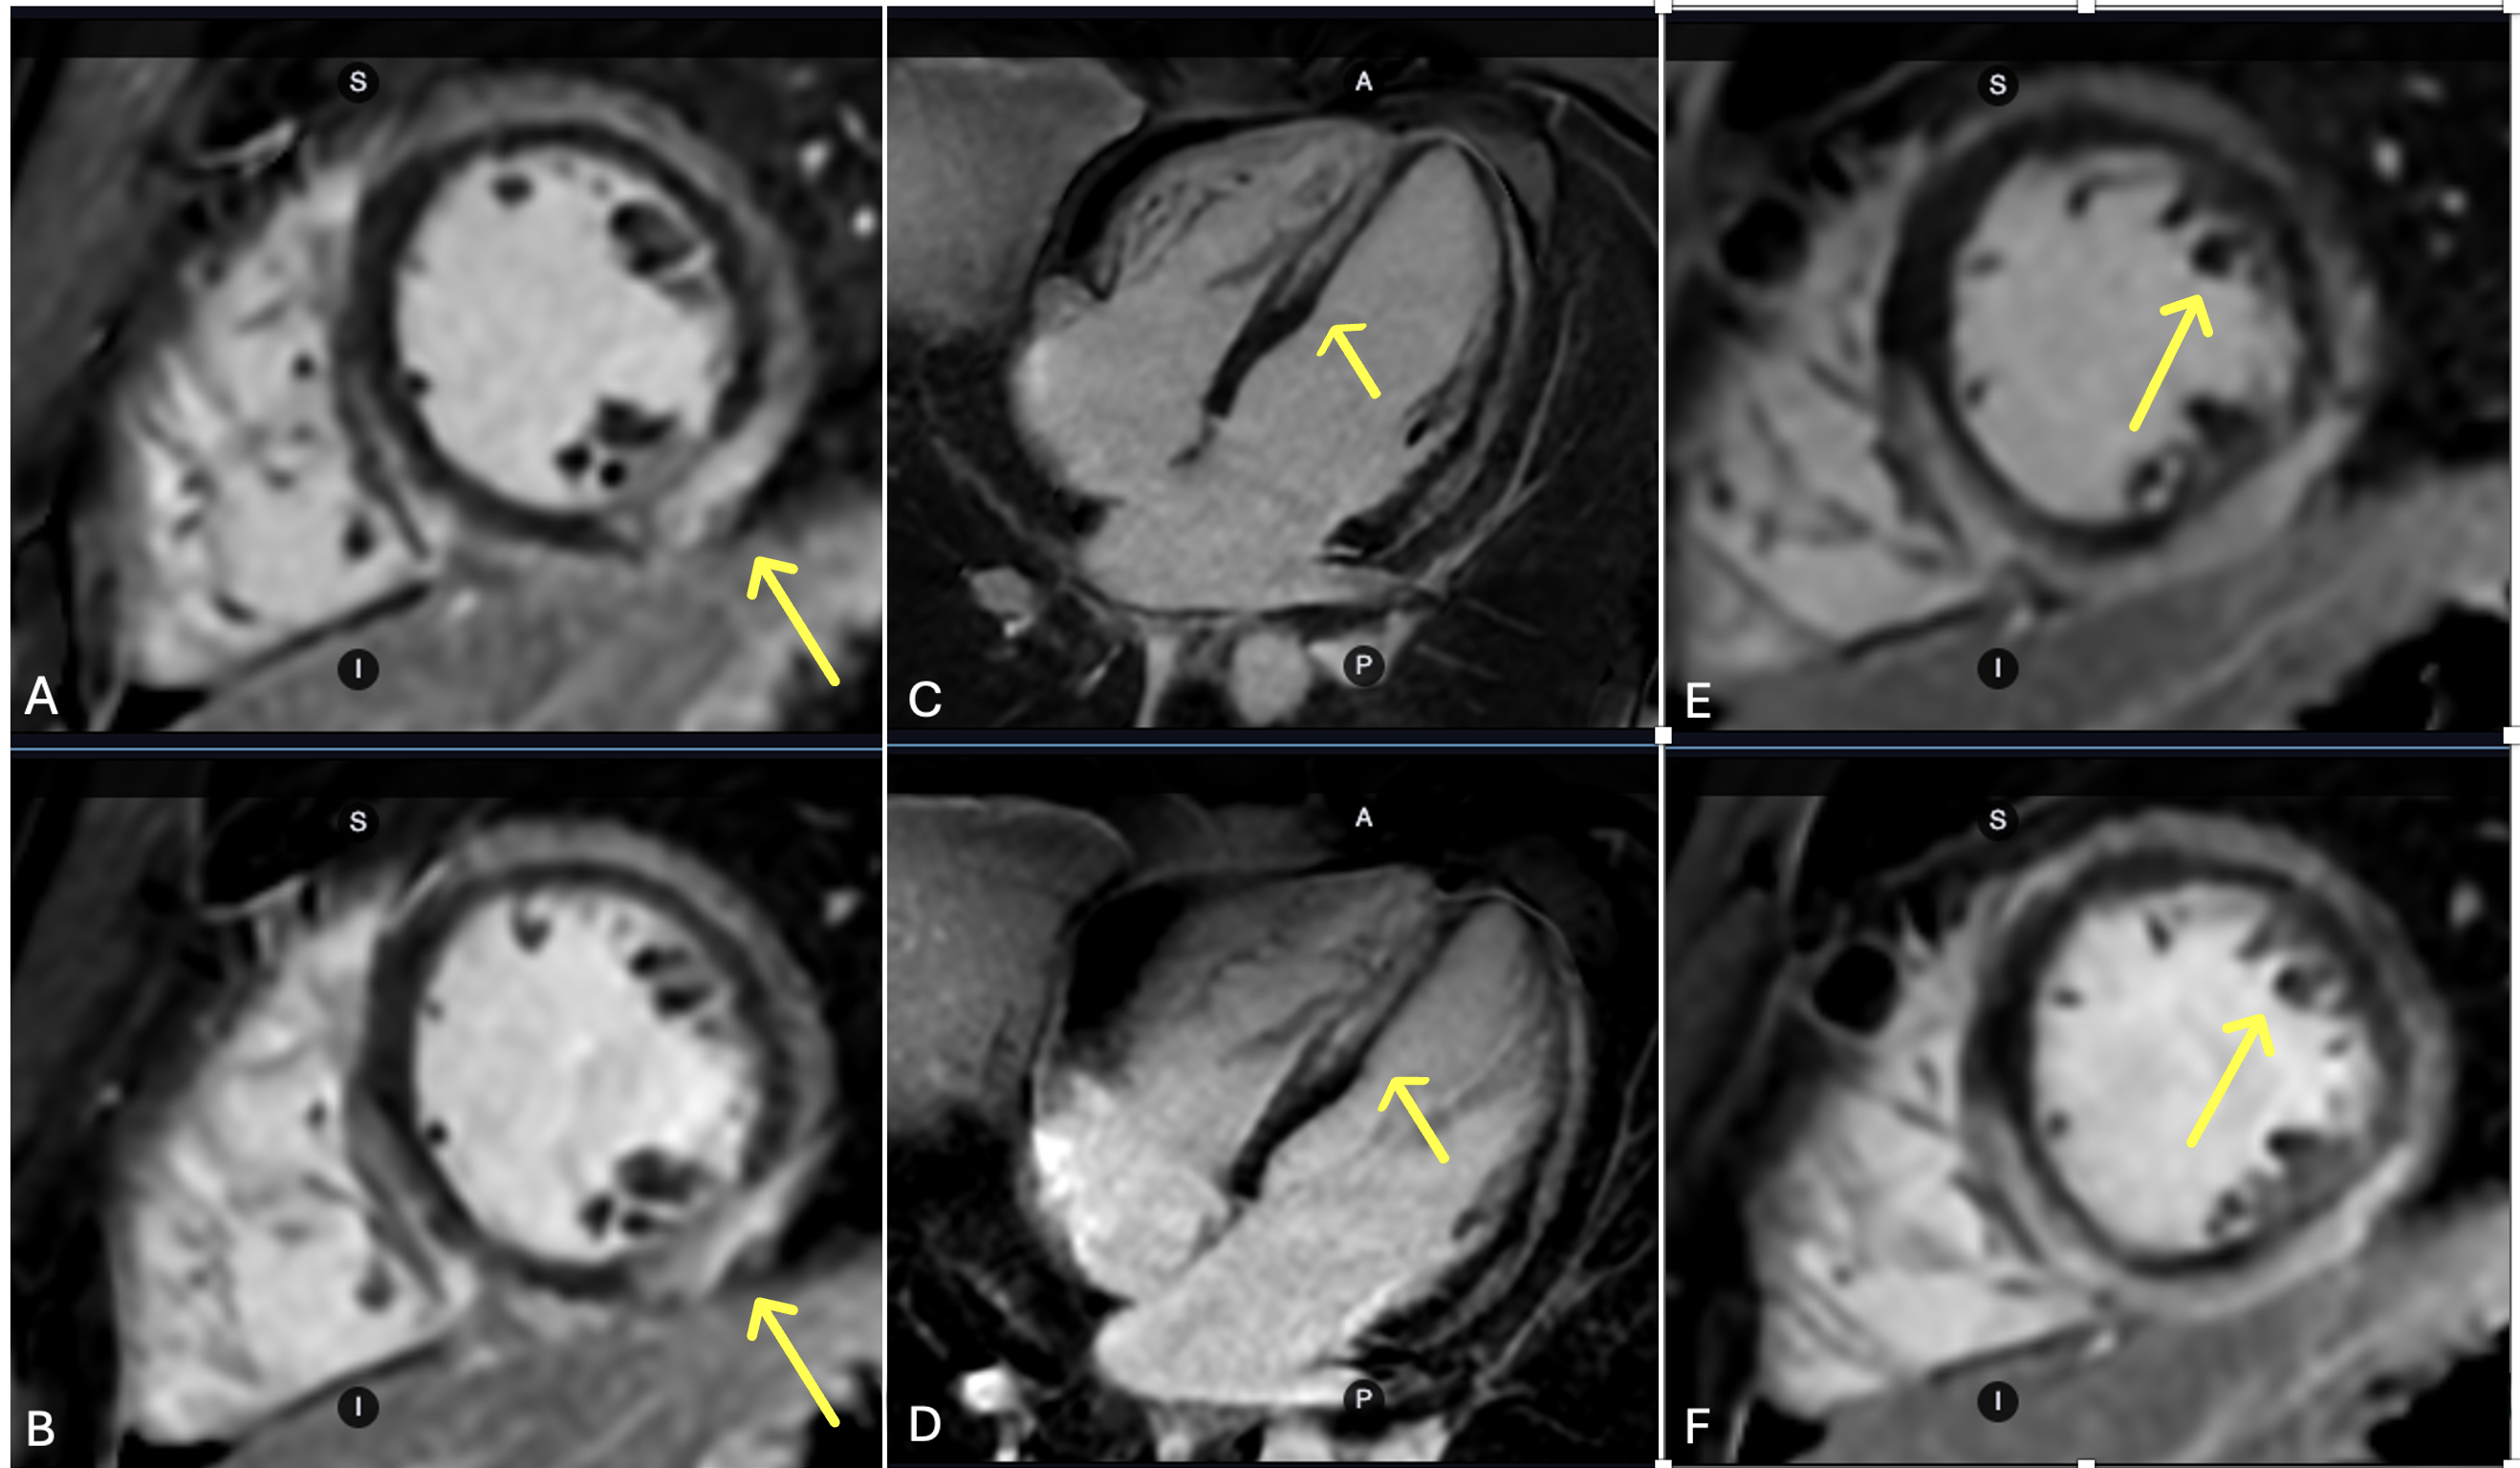

Figure 1. Representative ssh PS LGE images from a 19-year-old male patient acquired during the 6-month follow-up. The patient presented to the emergency department with one week history of cough, fever, and chest pain. His cardiac MR findings were consistent with acute myocarditis including myocardial edema with elevated T2 value, elevated T1/ECV value, and extensive delayed enhancement. Patient returned 6 months later for follow up with resolution of parametric mapping abnormalities and persistent delayed enhancement. Ssh PS LGE images acquired with the enhanced protocol (A, C, E) demonstrate improved image sharpness and decreased image blur compared to those acquired with the conventional protocol (B, D, F), as highlighted by the yellow arrows.